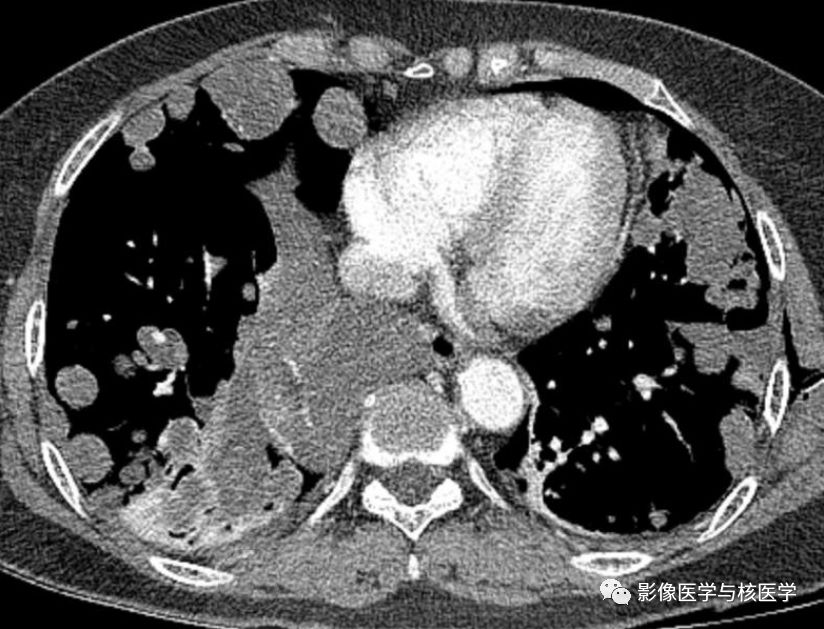

图2 胸部CT增强

图4 胸部CT增强

Figure 2-4. On chest CT after chest tube insertion in left hemithorax, there are multiple nodules and masses with/without cavity in both lungs.

图2-4.胸部CT显示左侧气胸置管后,两肺多发结节或肿块伴或不伴空洞。